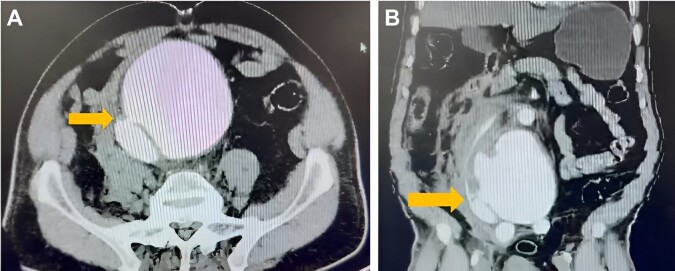

在腹主动脉瘤的范围内,可能出现各种并发症,包括将这条主要血管与肾下腔静脉连接起来的动静脉瘘的发展。本文报告一例70岁男性患者,因腹主动脉瘤破裂而出现突然剧烈腹痛和晕厥,术中发现主动脉腔瘘。患者接受了紧急护理,包括瘘管关闭和放置涤纶主动脉股动脉移植物。主动脉腔瘘是一种罕见的主动脉瘤疾病并发症,其临床表现因疾病进展而异,导致手术或介入治疗前后的高发病率和死亡率。

Within the spectrum of abdominal aortic aneurysm, various complications can arise, including the development of an arteriovenous fistula connecting this major vessel to the infrarenal inferior vena cava. This report presents the case of a 70-year-old man with sudden, intense abdominal pain and syncope, found intraoperatively to have an aortocaval fistula due to a ruptured abdominal aortic aneurysm. The patient underwent emergency care, including fistula closure and placement of a Dacron aortobifemoral graft. Aortocaval fistula is a rare complication of aortic aneurysmal disease, with clinical manifestations varying depending on disease progression, leading to high morbidity and mortality both before and after surgical or interventional treatment.